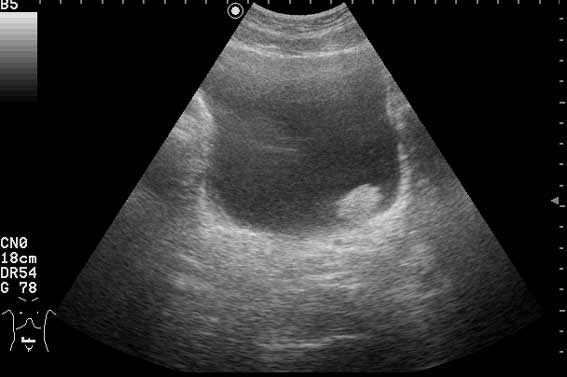

Ну конечно же, на представленных эхограммах - папиллярная опухоль мочевого пузыря.

Писать в заключении, что это полип - нельзя, это случай при котором руководствуются правилом - считаем опухоль злокачественной, пока не доказано обратное. Опухоль расположена над устьем левого мочеточника, нет обструкции устья и терминального отдела мочеточника (доказательство - наличие полноценного выброса мочи из устья) - что, в свою очередь, говорит против интралюминальной уретеральной опухоли.